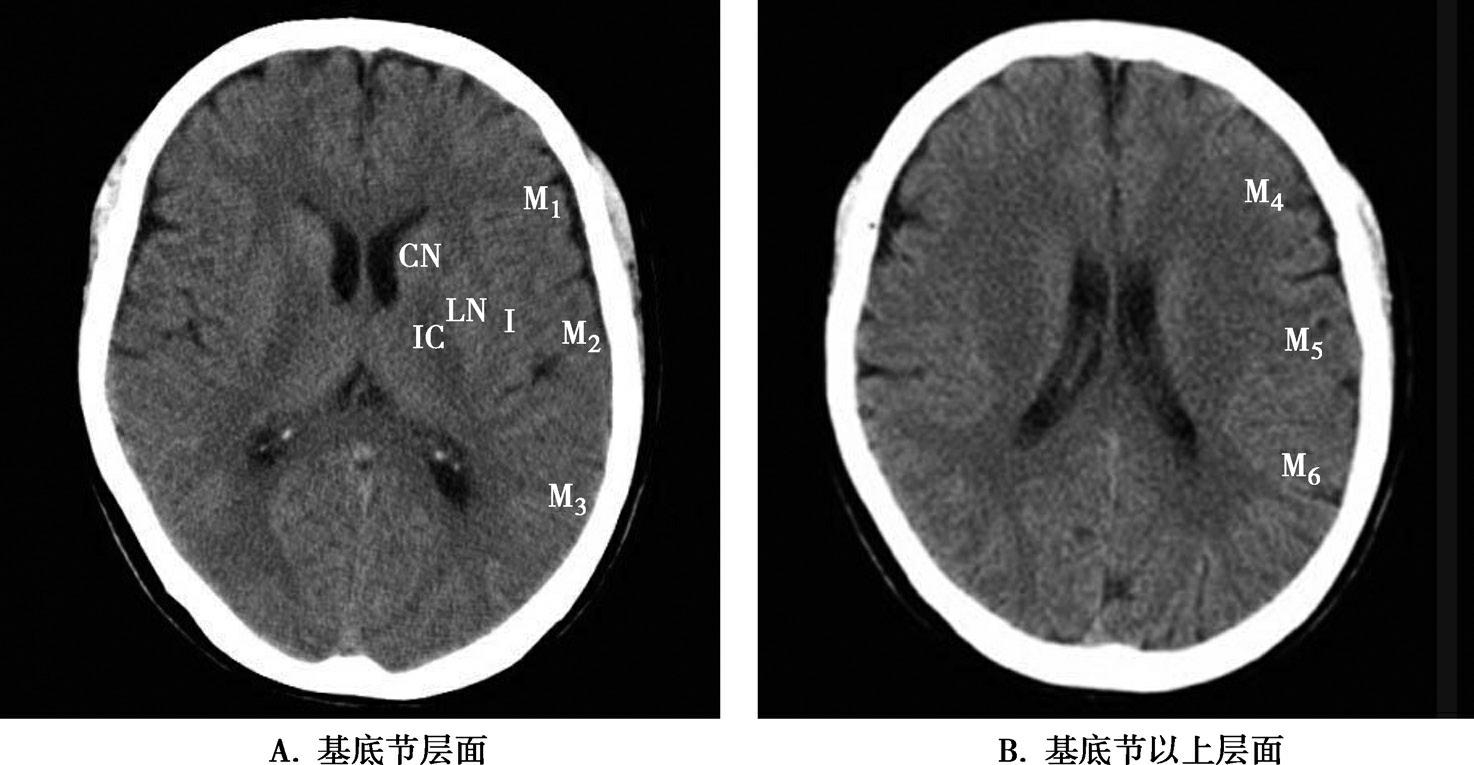

Alberta卒中项目早期CT评分(Alberta stroke program early CT score,ASPECTS)是一种评价急性缺血性卒中患者大脑中动脉供血区早期缺血性改变的简单、可靠、系统化的方法,是常用的脑卒中评定量表之一,可对缺血性病变快速进行半定量评价,有助于判定溶栓效果和远期预后。该评分主要基于CT平扫,具体分区如下(图1-2-76)所示,即选取大脑中动脉供血区2个层面。分区后共10个区域,每个区域记1分。评分时任何区域只要有低密度灶,则扣除该区域得分。正常脑ASPECTS评分为满分(10分),若MCA供血区广泛梗死累及全部区域时,则ASPECTS评分为0分。

图1-2-76 ASPECTS评分脑组织分区

A.在基底节层面(即丘脑和纹状体平面),分为各级分支M 1 、M 2 、M 3 、岛叶(缩写I)、豆状核(缩写L)、尾状核(缩写C)和内囊(缩写IC)后肢等7个区域;B.在基底节以上层面(基底节层面上2cm),包括M 4 、M 5 和M 6 。